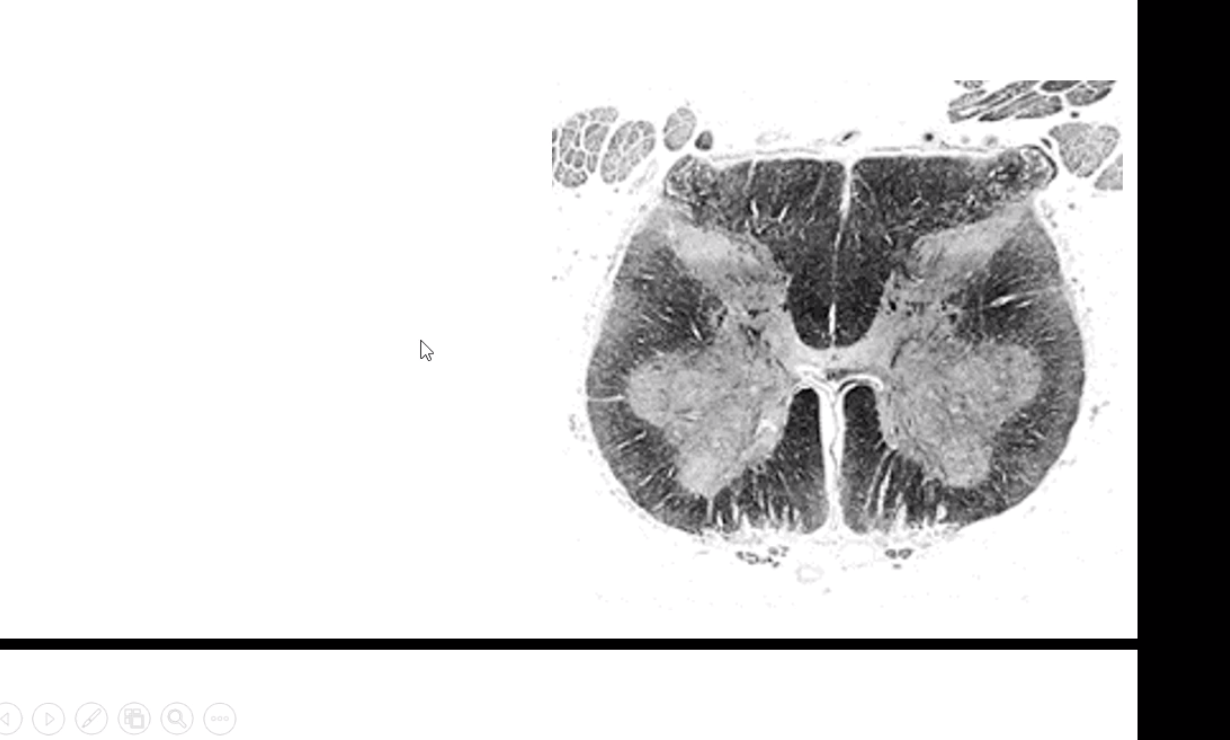

What spinal cord level is this?

What are the feautures of it?

Why does lumbar have less white matter than grey matter?

All the corticospinal axons from upper body have peeled off by then. Also just starting to bring in sensory information, so very few fibers. As you get higher you will get more white matter